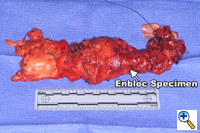

A right fifth interspace thoracotomy is performed regardless of the location of the tumor within the esophagus. The "first field" comprises the middle and lower mediastinum and is bounded superiorly by the tracheal bifurcation, inferiorly by the esophageal hiatus, anteriorly by the hilum of the lung and pericardium and posteriorly by the descending thoracic aorta and the spine. The en-bloc resection of the middle and lower mediastinum begins by incising the mediastinal pleura over the anterior aspect of the azygous vein from the level of the azygous arch superiorly to the aortic hiatus inferiorly. The dissection proceeds leftwards anterior to the aorta and across the mediastinum to the opposite pleura, which is entered along the entire length of the incision. The thoracic duct is thus mobilized anteriorly towards the specimen and is ligated inferiorly at the aortic hiatus and superiorly as it crosses to the left side of the mediastinum (Figure 1). The arch of the azygous vein, but not its main trunk, is resected en-bloc with the specimen. The anterior dissection is commenced by division of the azygous vein at its caval junction and by carrying the dissection along the right main bronchus and the posterior aspect of the hilum of the right lung. The hilar and subcarinal nodes are cleared and a patch of pericardium is resected en-bloc with the tumor-bearing esophagus if the latter abuts the pericardial sac.

Division of both pulmonary ligaments (left and right) completes the esophageal mobilization (Figure 2). For tumors traversing the hiatus, a one-inch cuff of diaphragm is circumferentially excised en-bloc with the specimen using electrocautery. The completed dissection clears all nodal tissue in the middle and lower mediastinum including the right and left paraesophageal, parahiatal, para-aortic, subcarinal, bilateral hilar, and aortopulmonary lymph nodes.

Dissection of the "third-field" begins during the thoracic portion of the procedure and is later completed through a collar neck incision. Dissection of the nodes in the superior mediastinum includes the nodes along the right and left recurrent laryngeal nerves throughout their mediastinal course. The paratracheal retrocaval compartment is not disturbed. The left recurrent nerve is dissected using a "no-touch" technique and nodes along its anterior aspect are carefully excised (Figure 3). Notably, there is a paucity of nodal tissue along the left nerve in nearly all Caucasians. The right recurrent nerve is carefully exposed near its origin at the base of the right subclavian artery. The right recurrent nodal chain begins at that level and forms a continuous package that extends through the thoracic inlet to the neck. Again, the nerve is dissected using a strict "no-touch" technique (Figure 4). Through the cervical incision, the remainder of the recurrent nodes are dissected as are the lower deep cervical nodes located posterior and lateral to the carotid sheath. Thus the "third-field" includes a continuous anatomically inseparable chain of nodes that extends from the superior mediastinum to the lower neck. These nodes should be appropriately labeled cervicothoracic (CT) nodes rather than cervical nodes.

The abdomen is entered through a mid-line incision. The omentum is separated from the colon in the avascular plane and the lesser sac is entered. Following division of the short gastric vessels, the retroperitoneum is incised along the superior border of the pancreas. The retroperitoneal lymphatic and areolar tissues are swept superiorly towards the esophageal hiatus and medially along the splenic artery to the celiac trifurcation. The left gastric artery is divided flush with its celiac origin and the nodes along the common hepatic artery are dissected towards the specimen. This retroperitoneal dissection is bounded by the dissected esophageal hiatus superiorly, the hilum of the spleen laterally and the common hepatic artery and inferior vena cava medially (Figure 5). Finally, the lesser curvature and left gastric nodes are included with the specimen as the gastric tube is prepared. The omentum is resected as a separate specimen at least one inch outside the gastroepiploic arcade.

A generous low collar incision is performed and subplatysmal flaps are raised inferiorly and superiorly. The strap muscles and the medial heads of the sternocleidomastoid are divided. The esophagus (previously fully mobilized from the thorax) is retrieved from the prevertebral space. The esophagus is divided distally and the specimen is retrieved in the abdomen. The previously dissected recurrent nerves are easy to visualize (especially the right recurrent) and any residual nodal tissue is excised (Figure 6). Next, the nodes posterior and lateral to the carotid sheath are removed along with the supraclavicular nodes (Figure 7). The dissection is limited superiorly by the inferior belly of the omohyoid. Within the abdomen the gastric tube is prepared and the specimen is removed (Figure 8). Gastrointestinal continuity is restored by a cervical esophagogastrostomy.